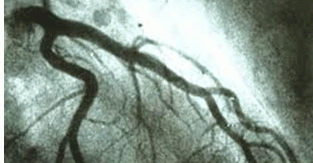

目前的研究尚未发现冠心病的确切病因,很多因素可以引起冠心病,也就是说冠心病的病因是多因素的,因此,这些病因又叫做高危因素。冠心病的高危因素有很多,如年龄、性别、家族史〔即遗传因素〕、高血压、吸烟、高脂血症等。在这些因素中高血压、吸烟、高脂血...

冠心病的病理基础是冠状动脉硬化,是属于发病率高的进展性慢性疾病,所以冠心病具有复发率高的特点。冠心病预防包括一级预防(对未发生冠心病疾病的危险人群而言)和二级预防(对已经得了冠心病的患者而言),预防措施无论对冠心病患者或冠心病高发危险人群都...